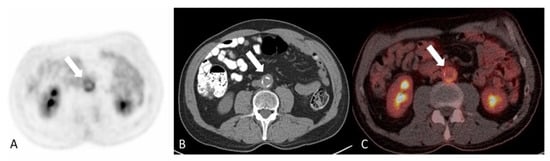

2.2. Medium-Vessel Vasculitis

2.2.1. Polyarteritis Nodosa